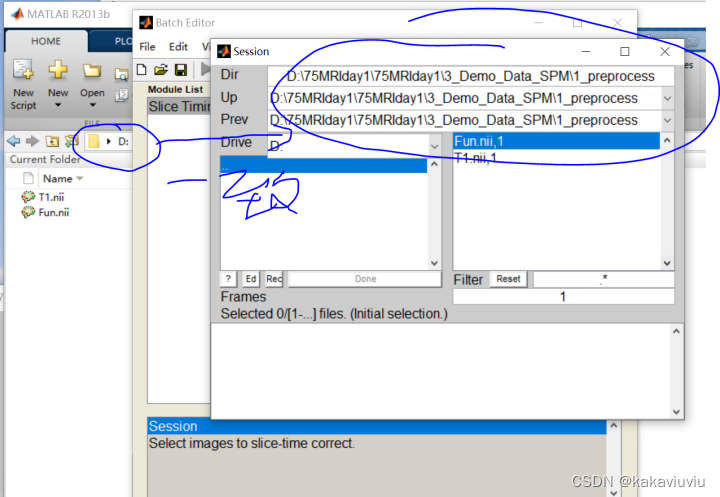

打开spm,点击slice timing--data--点击session

导入进nii文件,注意把右下角的1换为inf(无限的意思),然后右键--select all

(可以提前把matlab的路径设置成存放文件的路径,这样方便选择)

frame:1 --第一帧的图像 ,一般写成inf(无穷,可以包含所有的图像)

filter旁边的白色长空格可以输入文件名来筛选文件

选完点done